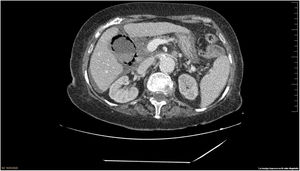

La TC abdominal con contraste muestra áreas en vidrio esmerilado bilaterales, periféricas, basales pulmonares, sugestivas de SARS-CoV-2 con PCR negativa. Vesícula biliar distendida con paredes llenas de aire y con barro biliar con líquido perihepático y pélvico (fig. 1).

Se (fig. 2) descarta cirugía por elevada morbimortalidad, consensuando tratamiento conservador con antibióticos. Exitus a las 24 h del ingreso.

Diagnóstico: colecistitis enfisematosa.